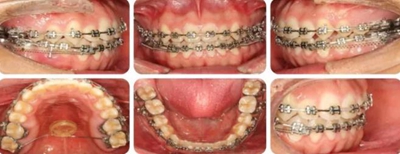

結(jié)束時(shí),可見前牙覆合覆蓋正常,上下牙列排齊,雙側(cè)尖磨牙達(dá)到中性關(guān)系。

高角反頜伴開頜病例,多采用正畸正頜聯(lián)合治療。但該患者為直面型,下牙列輕度擁擠,下前牙直立,且年齡較小,手術(shù)治療非首選。采用種植釘內(nèi)收下前牙代償性治療前牙反合。而且需要拔除阻生智齒減小遠(yuǎn)移下牙列的阻力。

羅晨醫(yī)生:我今天展示的病例,技術(shù)創(chuàng)新在于種植釘整體遠(yuǎn)移下頜全牙列。臨床正畸治療中,對(duì)于反頜伴開頜的患者,一直是令人困擾的難題。以往的上頜骨嚴(yán)重發(fā)育不足的患者,只能通過正頜手術(shù)進(jìn)行改善,但一來患者比較痛苦,二來費(fèi)用較高,

給患者帶來很大的負(fù)擔(dān)。而本病例通過下頜頰棚區(qū)植入微種植釘,整體將下頜牙列內(nèi)收,引起下頜骨逆時(shí)針旋轉(zhuǎn),開合和反合得到了糾正,達(dá)到了良好的效果。